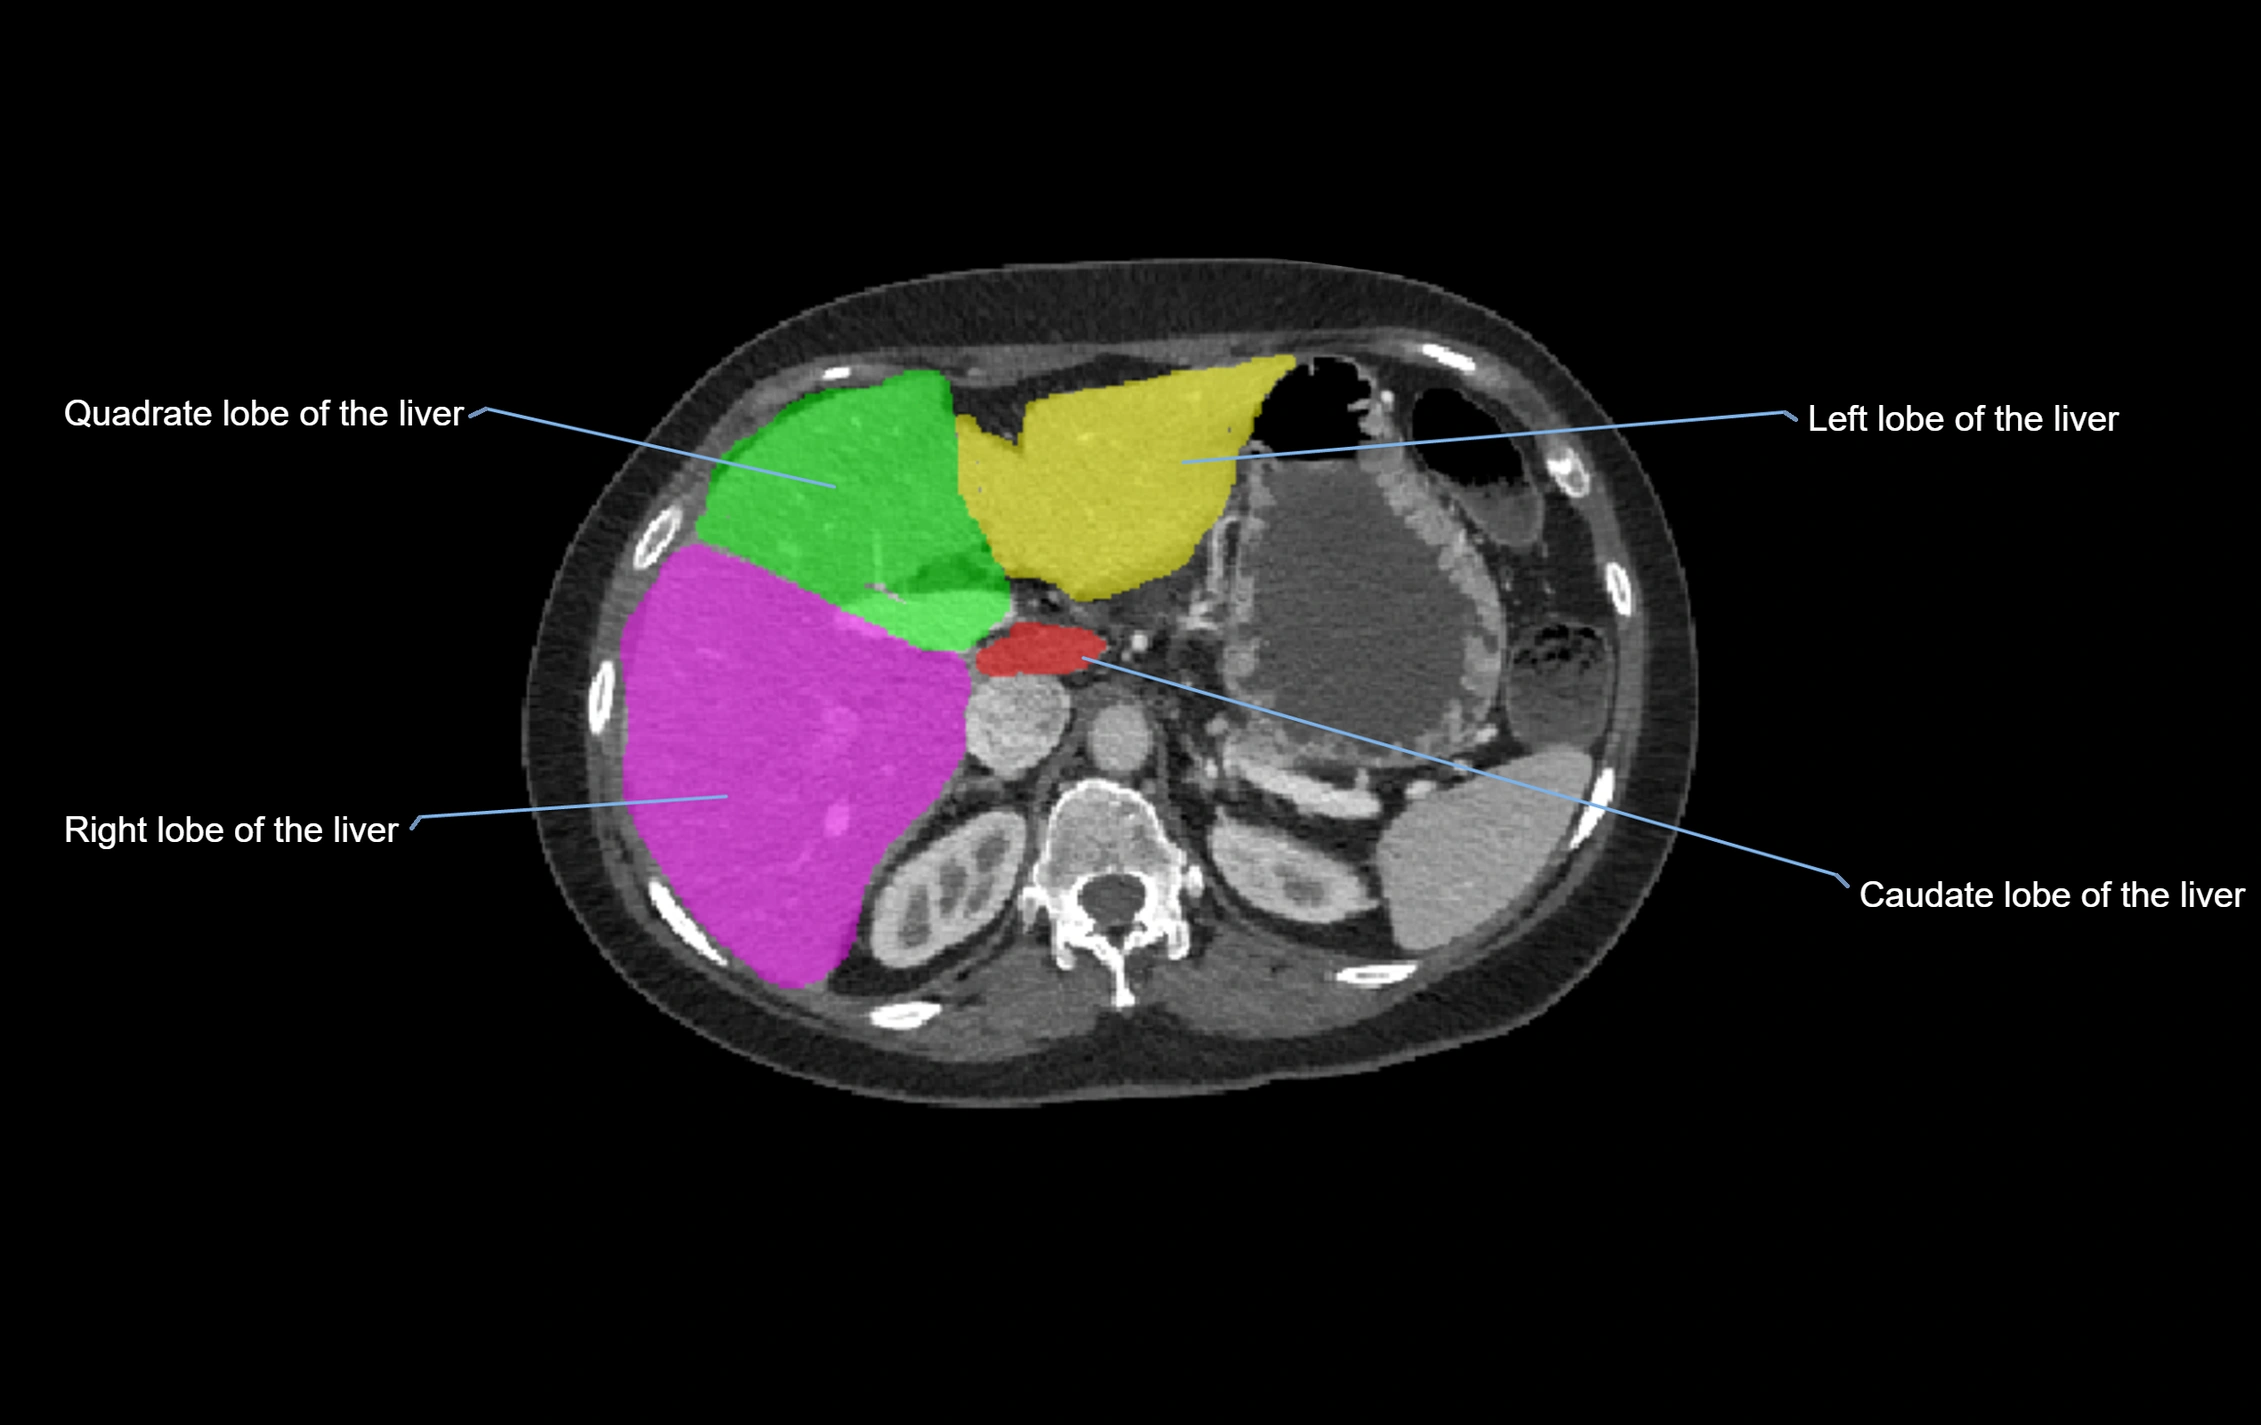

CT Appearance

CT Pre-Contrast:

• Caudate lobe appears as a soft-tissue density, isodense to the rest of the liver

• Enlargement may be appreciated in cirrhosis or Budd–Chiari syndrome

CT Post-Contrast:

• Homogeneous enhancement in the portal venous phase, similar to rest of liver

• Independent venous drainage into the IVC may be visualized

• Lesions follow characteristic CT enhancement patterns (HCC: arterial hyperenhancement with washout; hemangiomas: peripheral nodular enhancement with centripetal fill-in)

CT Venous Phase (functional significance):

• Caudate lobe often enhances relatively more than other lobes in Budd–Chiari syndrome, due to preserved venous outflow

CT Image

image